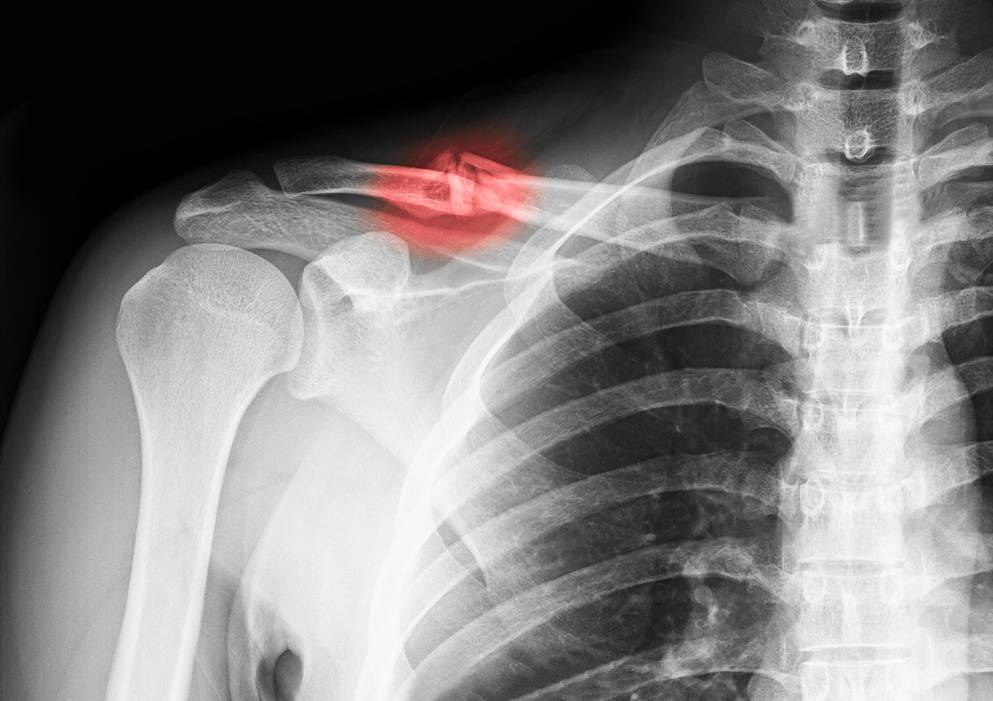

عظام الترقوة هي العظام التي تحمل الكتفين وتعمل على الربط بين الكتف وعظام القص، وهي موجودة على كلا الجانبين من الجسم، ويمكن أن تحدث الإصابة في عظمة الترقوة بعد السقوط القوي أو التصادم العنيف في الكتف مما يؤدي إلى تعرض العظمة للصدمة وحدوث كسر وغالبا ما يكون في المنتصف.

تشيع كسور عظمة الترقوة في الأطفال ويمكن أن يصاب بها البالغين أيضا خاصة ممارسي الرياضة، ويمكن أن تكون كسور الترقوة نوعين وهما:

الكسور التي لا يتحرك العظم فيها من مكانة وبالتالي لا تؤثر على المنطقة المحيطة بها، وكسور أخرى مُنزاحة والتي تتحرك العظام فيها من مكانها مما يؤثر على الأربطة والعضلات المحيطة بموقع الإصابة.

يتم الكشف عن وجود كسر في الترقوة من خلال قيام الطبيب بفحص بدني دقيق للمنطقة المصابة، حيث يبحث عن علامات مثل الألم والتورم والتشوه في شكل العظمة.

يتم إجراء صورة بالأشعة السينية لتحديد موقع الكسر بدقة ونوعه، مما يساعد في وضع خطة علاج مناسبة.